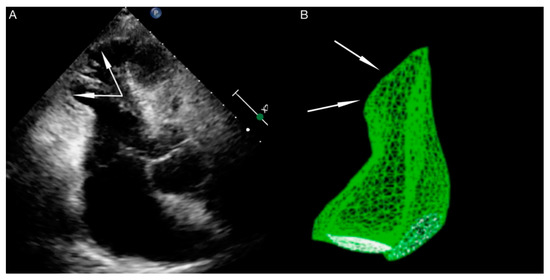

- Opolski, G.; Kochanowski, J.; Torbicki, A.; Scisło, P.; Kowalik, R.; Piotrowska-Kownacka, D.; Zarebiński, M.; Pruszczyk, P.; Kalarus, Z. The recurrence after ten years—“Mother in-law variant” of tako-tsubo syndrome. Kardiol. Pol. 2010, 68, 557–561. [Google Scholar]

- Opolski, G.; Budnik, M.; Kochanowski, J.; Kowalik, R.; Piatkowski, R.; Kochman, J. Four episodes of takotsubo cardiomyopathy in one patient. Int. J. Cardiol. 2016, 203, 53–54. [Google Scholar] [CrossRef]